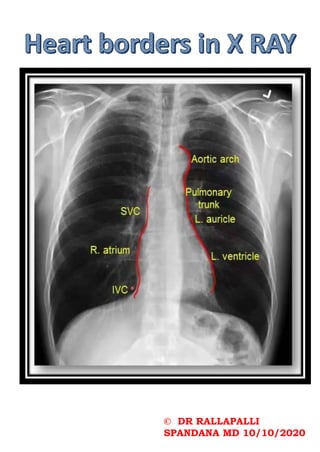

CXR PA VIEW CXR AP VIEW

TFD – 6 FEET TFD- Short

Parallel X ray beams Divergent x ray beam

Distance between heart and

film - small

film - large

Cardiac shadows not

magnified

Cardiac shadows –

False cardiomegaly

Done for anterior chest wall Done for posterior chest

wall

Posterior elements of

vertebrae

Disc spaces/vertebral bodies

Short exposure time More exposure time

Causes motion artifacts